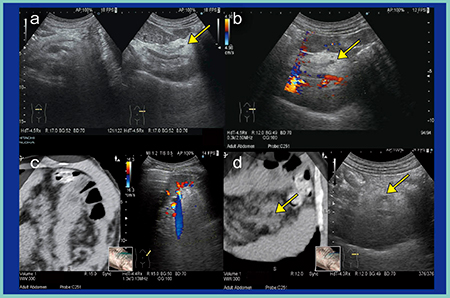

次に,RVSを活用した小病変の描出のポイントを述べる。図4は,膵尾部に小さな膵管内乳頭粘液性腫瘍(IPMN)が認められる(図4 a,b)。左肋間からの走査では脾静脈は確認できるものの膵臓はガスにより非常に見えづらいため(図4 c),左の季肋部から左の側腹部に向けた横走査を行うことで,小さな病変の観察も容易となる。CT画像と比較すると,病変部は超音波像と一致しており,RVSの精度の高さが実感できる(図4 d)。

図5は,膵尾部癌である。通常の肋間からの走査では確認できないが(図5 a),前述の通り,左の季肋部から左の側腹部に向けた走査を行うことで,仰臥位での観察が可能である(図5 b,c)。また,被検者に深呼吸をしてもらうと,吸気時の腹圧の上昇によりプローブに近いところに膵臓が位置するため,観察しやすくなる。右側臥位からの走査も有用である(図5 d)。

図4 RVSを活用した小病変の描出のポイント

図5 超音波による膵尾部癌の描出